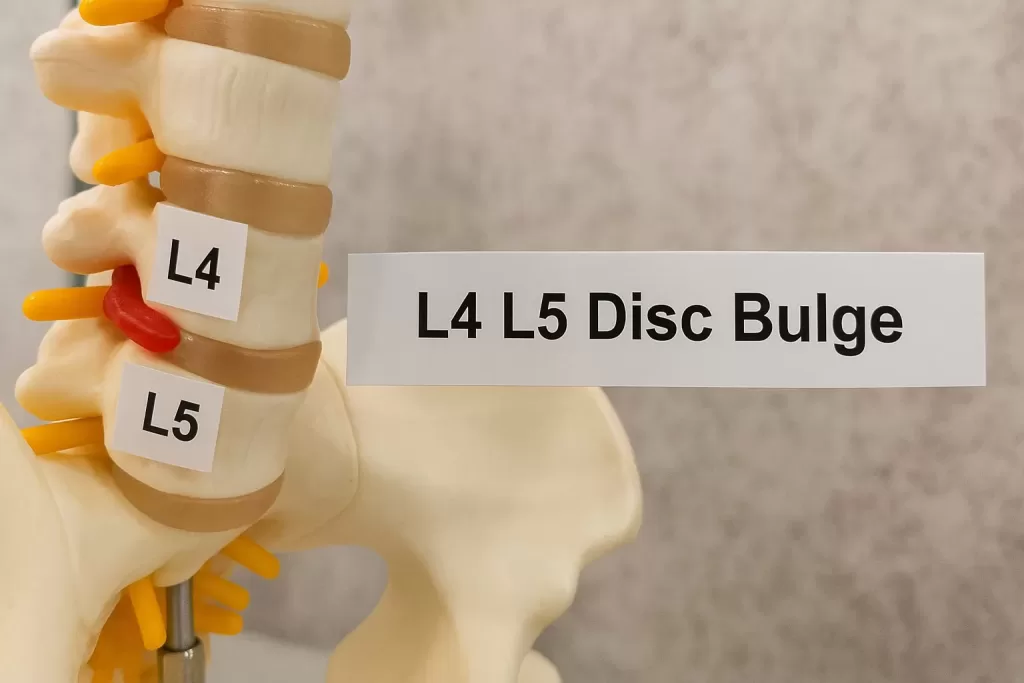

L4 L5 Disc Bulge Treatment

Struggling with lower back pain radiating into your legs? Learn what an L4 L5 disc bulge means and how it affects you. Read More

L5 S1 Disc Bulge Treatment

Lower back pain and stiffness? An L5 S1 disc bulge is one of the most common causes — discover why it happens and what it means. Read more